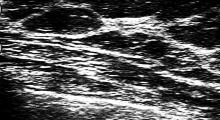

Brustentzündung: Ultraschall und Tastbefund

Zur Diagnose einer Brustentzündung werden verschiedene Untersuchungen und Abklärungen durchgeführt. Dazu gehören unter anderem:

• Ultraschall